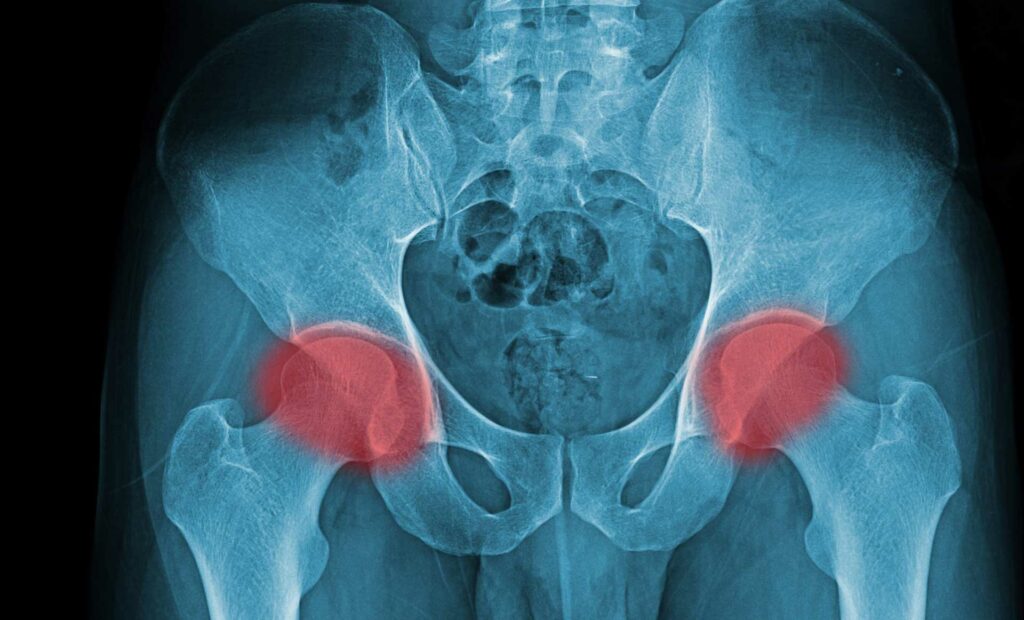

LA RESISTANCE A L’INSULINE (10) Les douleurs en tout genre et les bénéfices de l’acupuncture (3) Résistance à l’insuline et douleurs articulaires, notamment aux mains Le diabète et les douleurs articulaires sont des affections courantes qui touchent de nombreuses personnes à travers le monde[1]. Le diabète peut entraîner en effet diverses complications, y compris […]

LA RESISTANCE A L’INSULINE (10) Les douleurs en tout genre et les bénéfices de l’acupuncture (1) Insulino-résistance et douleur (chronique) Les études épidémiologiques et méta-analyses montrent une forte relation entre la douleur, notamment lorsqu’elle devient chronique et les anomalies du métabolisme du glucose. Les recherches montrent que vivre avec une douleur chronique affecte tous les […]